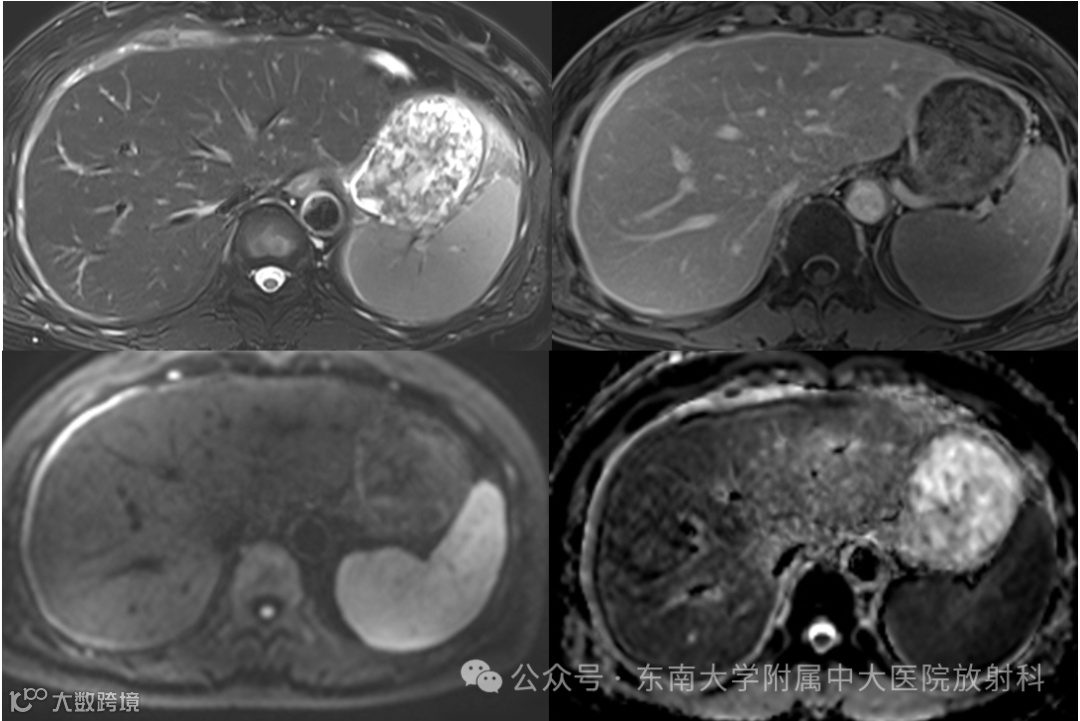

病例1

现病史:患者一月余前无明显诱因出现右上腹痛,伴有全身肌肉酸痛,自觉发热,体温未测,自行口服“白加黑”后全身酸痛好转,腹痛改善不明显,后口服“甲硝唑片”,腹痛稍有改善,深呼吸时加重,偶有头痛,食欲下降,遂至外院住院治疗,住院期间未予特殊治疗。现患者仍有上腹部疼痛,较前稍缓解,为进一步诊治来我院。患者无畏寒发热,无体重消瘦,否认“肝炎”、“结核”、“伤寒”等传染病史 -

影像学表现